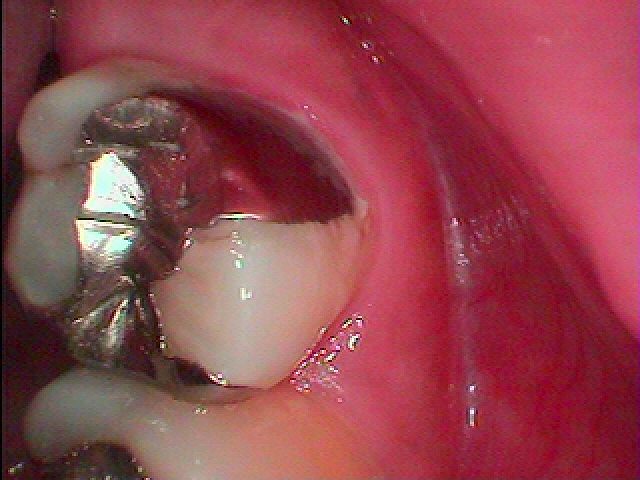

ブログ一覧|広島市安佐南区の歯科医院 ブログ一覧 トップ ブログ一覧 お知らせ スタッフブログ ブログ一覧 お知らせ 2021/03/08 右上7番のセラミック治療 銀歯を外して虫歯治療 お知らせ 2021/03/08 右上6,7,8番の一般治療 8番は抜歯 7,6番は根の治療から お知らせ 2021/03/06 インプラント埋入後2か月になります 上部構造を立てていきます お知らせ 2021/03/06 右上5番が噛むと痛みだしてきた診てほしい 歯も動くように感じる お知らせ 2021/03/05 アバットメントを合わせていきました 上部構造は今回オールセラミックにて作成を行っていきます お知らせ 2021/03/05 右下5番にインプラントを埋入していきます ブリッジは嫌とのこと 長持ちする設計でやってほしい お知らせ 2021/03/04 右下の銀歯を外して虫歯治療 右下7番になります お知らせ 2021/03/04 左上の銀歯2本を外して白いセラミックへやり変えていきます << 1 2 3 4 5 … 280 281 282 283 284 … 870 871 872 873 874 >> Web診療予約 初めての方へ 選ばれ続ける理由 院内設備について 歯が痛いしみる一般歯科 歯がぐらぐらする歯周病 健康な歯を保ちたい予防歯科 子供の虫歯予防をしたい小児歯科 銀歯をセラミックに審美歯科 白い歯を目指しませんか?ホワイトニング 矯正専門医がいるので安心矯正歯科 抜けた歯を補いたいインプラント・入れ歯 医院案内 スタッフ紹介 メリィハウス歯科クリニックオフィシャルホームページ ラベンダー歯科クリニックオフィシャルホームページ お知らせ・ブログ ホーム 診療科目 一般歯科 歯周病治療 予防治療 小児歯科 審美治療 ホワイトニング 矯正歯科 入れ歯・インプラント マウスピース矯正 初めての方へ 院長・スタッフ 設備紹介 医院案内・アクセス メニューを閉じる